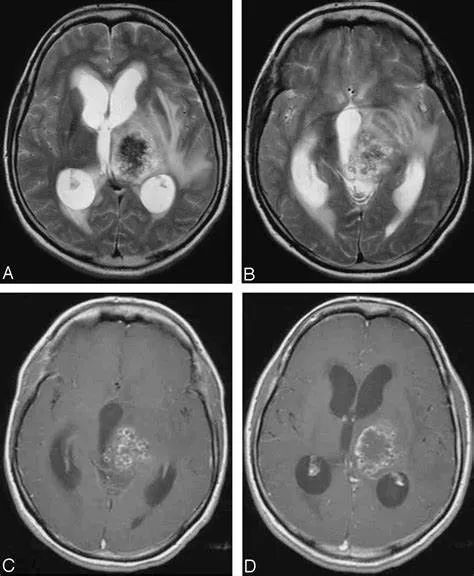

脑泡型包虫病影像学表现: 医学百科网 | YxBaike.Com

CT:类圆形或不规则形实性肿块,外周较中央部密度高,或呈略高密度肿块,病灶外周及中央部可发生钙化,周围水肿明显。

MRI:T1WI 呈等信号,T2WI 呈「煤炭样」黑色低信号(凝固性坏死),内可见多个大小不等或细小囊泡影(T2WI 高信号);周围常有水肿带;可有不规则环形强化,其内部可见细小强化浅淡的小分隔影,类似于「有厚沿的筛子」。 医学百科网 | YxBaike.Com

CT不均匀稍高密度,T1WI稍高信号,中心低信号,T2WI及FLAIR低信号,内部多发高信号,边缘不规则强化

T2WI低信号,内部多发小结节状高信号,边缘不规则强化 医学百科网 | YxBaike.Com